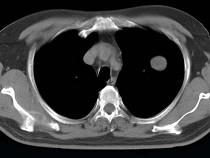

女性患者,42岁,1年前行肝癌手术,胸部CT扫描如图,应诊断为()A.肝癌肺转移B.肺结核球C.球形肺炎D.肺多发囊肿E.肺脓肿

问题 女性患者,42岁,1年前行肝癌手术,胸部CT扫描如图,应诊断为()

选项 A.肝癌肺转移 B.肺结核球 C.球形肺炎 D.肺多发囊肿 E.肺脓肿

答案 A